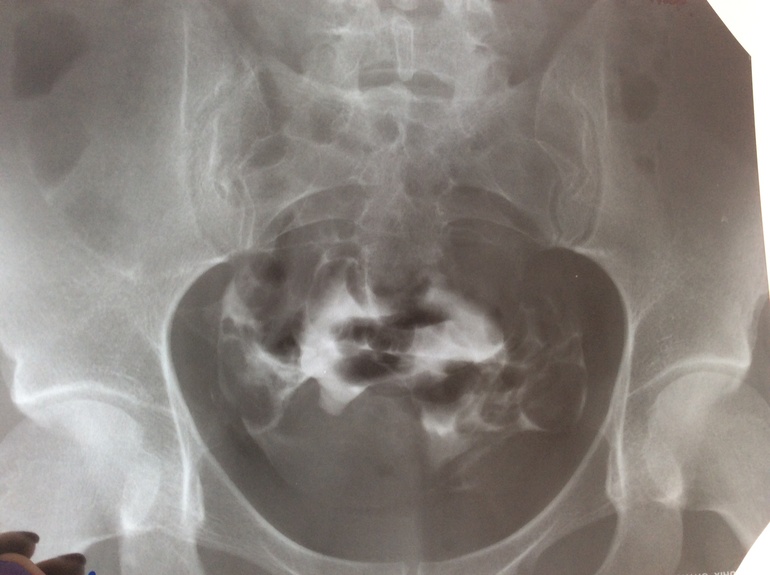

Здравствуйте! Мне 28. Планируем 2 года, анализы все хорошие,включая СГ. Отправили на гсг, трубы проходимы, но нашли подозрение на полипы на теле матки. УЗИ их не видит. Подскажите видите ли Вы их на этих снимках. Мне назначена стимуляция с 5 ДЦ. Вот я и думаю делать или искать полип дальше?! Заранее спасибо!

Здравствуйте! Скорее всего подозрение на полипы полости матки возникли из-за 2-х округлых дефектов на снимках, они отчетливо видны на 2 и 3 снимке, хотя это могут быть и пузырьки воздуха. Для исключения внутриматочной патологии необходима диагностическая гистероскопия (возможно, офисная)